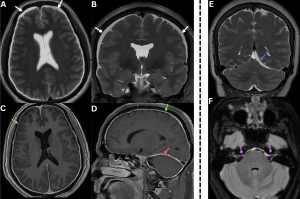

Fig 3: A 50-year-old with chronic orthostatic headaches and mild cognitive slowing.

Figures A and B: Coronal and Sagittal T2-weighted image shows prominent bilateral transverse sinuses with convex margins (white arrows) and bilateral subdural collections (red arrows).

Figure C: MR venogram confirms engorgement of the dural venous sinuses.

Fig 4: Figures A and B: Axial and coronal T2-weighted MR images demonstrating bilateral subdural hygromas (white arrows), seen as CSF-intensity fluid collections along the frontoparietal convexities.

Figures C and D: Axial and sagittal post-contrast T1-weighted images demonstrate diffuse smooth dural (green arrows) and tentorial (red arrow) enhancement over the bilateral cerebral hemispheres, consistent with pachymeningeal enhancement......Case 2—A patient with a chronic history of orthostatic headache, associated with neck stiffness and auditory symptoms, was evaluated for suspected spontaneous intracranial hypotension.

Figure E: Coronal T2-weighted MR image demonstrates a subdural collection along the left tentorium(blue arrow). {To our knowledge, tentorial subdural collection in spontaneous intracranial hypotension has not been previously described in the literature.}

Figure F: Axial T2/FLAIR MR image demonstrates dural thickening and hyperintensity along the brainstem and bilateral internal auditory canals(purple arrows).